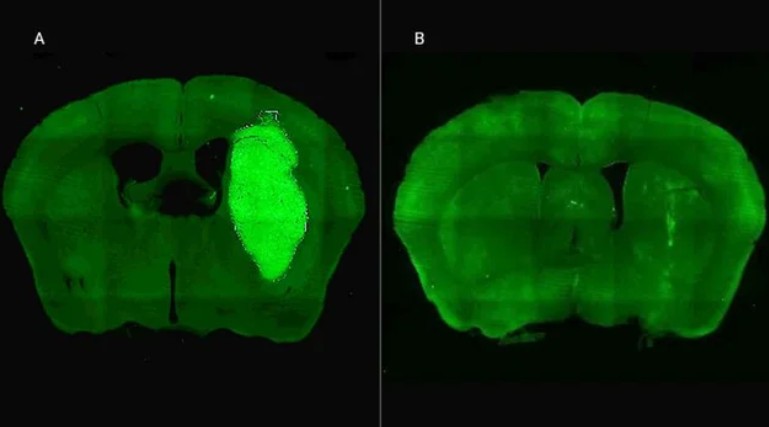

Además, P60 tuvo efectos antitumorales directos, reduciendo la viabilidad y la migración de las células de glioblastoma e inhibiendo la proliferación de células endoteliales que son clave para la progresión del tumor. Para evaluar estos efectos, los autores del estudio utilizaron una variedad de modelos celulares murinos (de roedor) y humanos. “En particular, los cultivos derivados de biopsias de pacientes con glioblastoma desarrollados por nuestro colaborador Guillermo Videla Richardson, del Instituto FLENI, son muy útiles para representar la heterogeneidad de estos tumores”, indicó Candolfi.